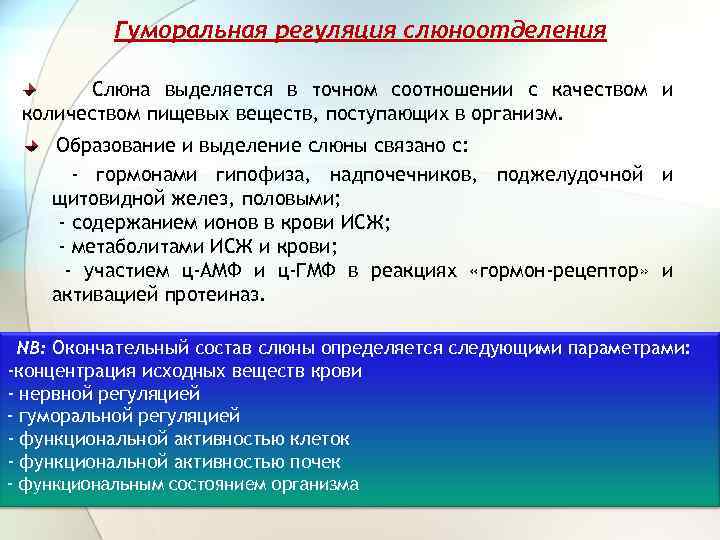

Гуморальная регуляция слюноотделения Слюна выделяется в точном соотношении с качеством и количеством пищевых веществ, поступающих в организм. Образование и выделение слюны связано с: - гормонами гипофиза, надпочечников, поджелудочной и щитовидной желез, половыми; - содержанием ионов в крови ИСЖ; - метаболитами ИСЖ и крови; - участием ц-АМФ и ц-ГМФ в реакциях «гормон-рецептор» и активацией протеиназ. NB: Окончательный состав слюны определяется следующими параметрами: -концентрация исходных веществ крови - нервной регуляцией - гуморальной регуляцией - функциональной активностью клеток - функциональной активностью почек - функциональным состоянием организма